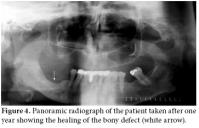

In September 2008, a 58-year-old female diagnosed with AS in 1973 was referred to Ege University Hospital, Department of Physical Medicine and Rehabilitation complaining of pain and discomfort in the right mandible. These symptoms had started in May 2008 following a tooth extraction. The extraction socket did not heal, even after eight weeks, despite antibiotherapy. Besides the pain and discomfort, she experienced the presence of some particles in the tooth extraction socket of her right mandible which were probably autogenous bone. A panoramic radiograph was taken 10 weeks later in July 2008 which revealed irregularity and diffuse sclerotic bone changes in the trabecular bone structure of the right mandible as well as a bony defect at the level of the extraction socket (Figure 1). A sample obtained from the exposed area was sent for culture to the microbiology laboratory due to the suspicion of dental infection/abscess. Oral flora microorganisms grew in the culture.

Together with the past history of long-term alendronate treatment and occurrence after tooth extraction, relevant clinical symptoms and conventional radiographic findings led to the suspicion of ONJ in this patient. We immediately ordered dental computed tomography (CT) which revealed sclerosis and osteolytic changes in the right mandible. This confirmed the diagnosis of osteonecrosis (Figures 2, 3). The patient also consulted with dental surgeons, and since there was no pathologic fracture, extra-oral fistulae, or osteolysis extending to the inferior border of the mandible, the disease was accepted to be in the second stage. Surgery was not recommended, and conservative management was started. The patient was advised to discontinue the alendronate treatment, and the etanercept treatment was also stopped. A good oral hygiene regimen using antibacterial tooth rinse was recommended. Her complaints and symptoms alleviated gradually. A control panoramic radiography taken after one year of bisphosphonate withdrawal displayed healing of the exposed bone (Figure 4).